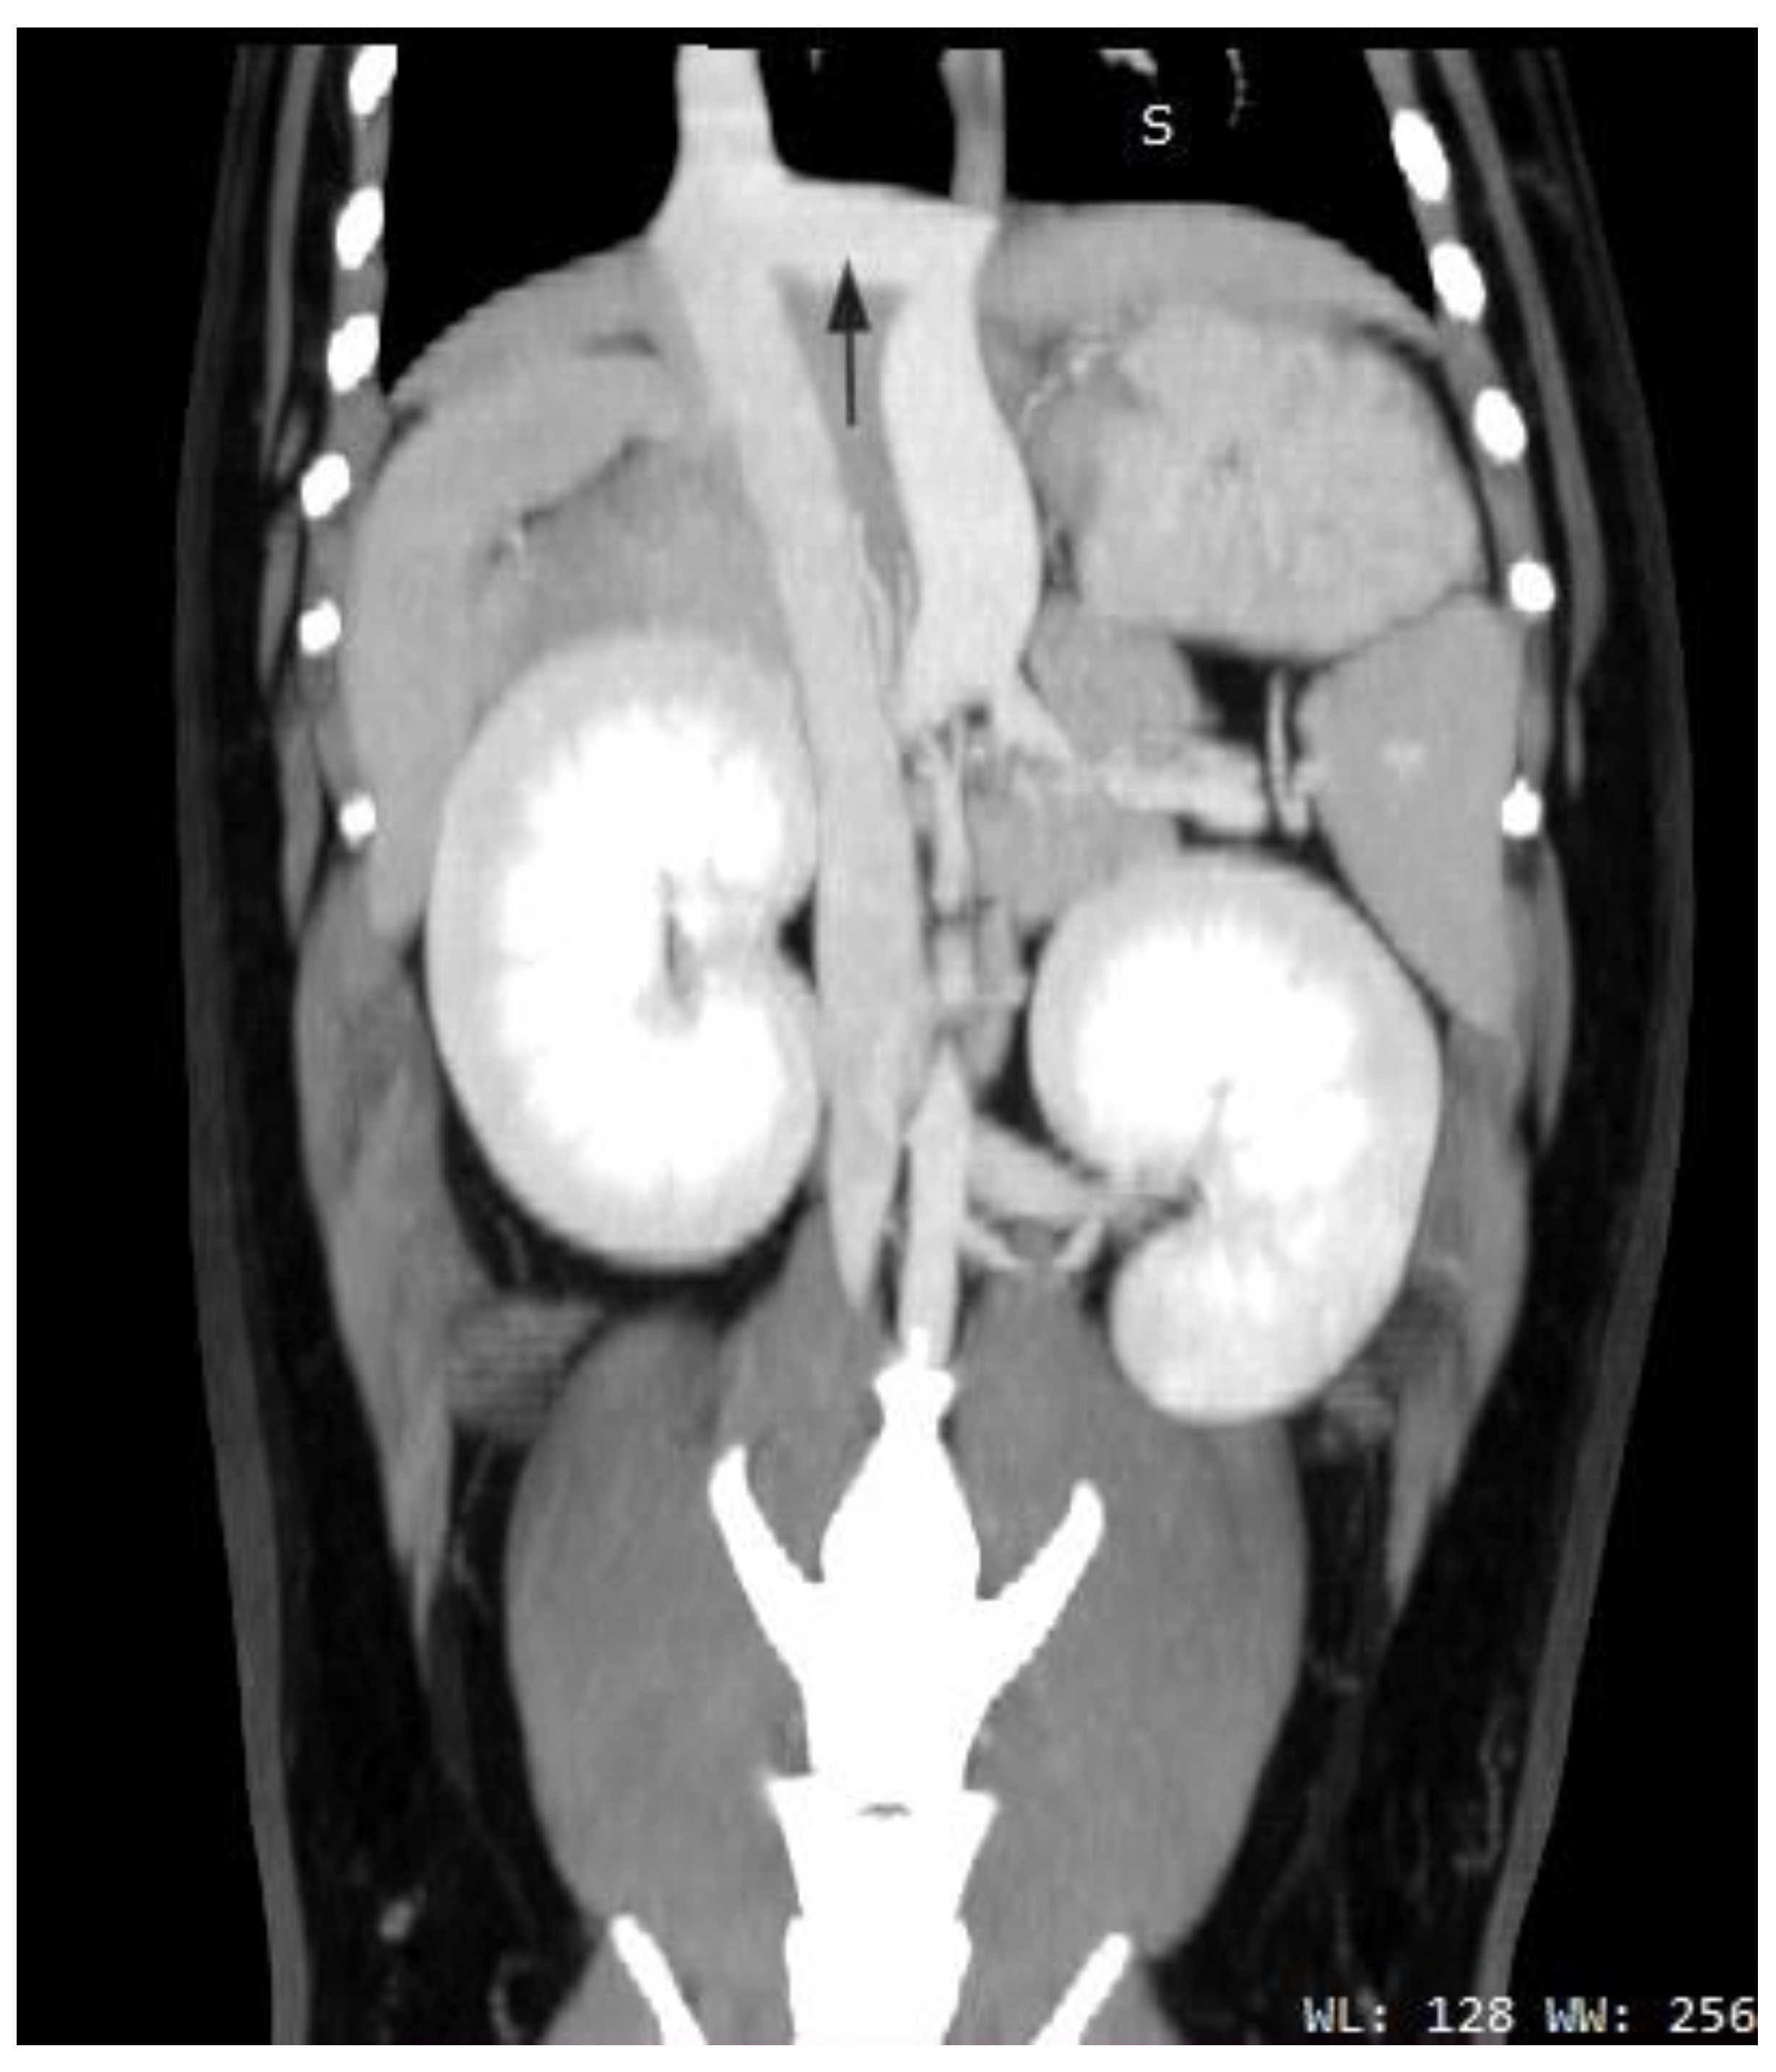

2.2. Case B (Human)

2.3. Case C (Dog)

2.4. Case D (Dog)